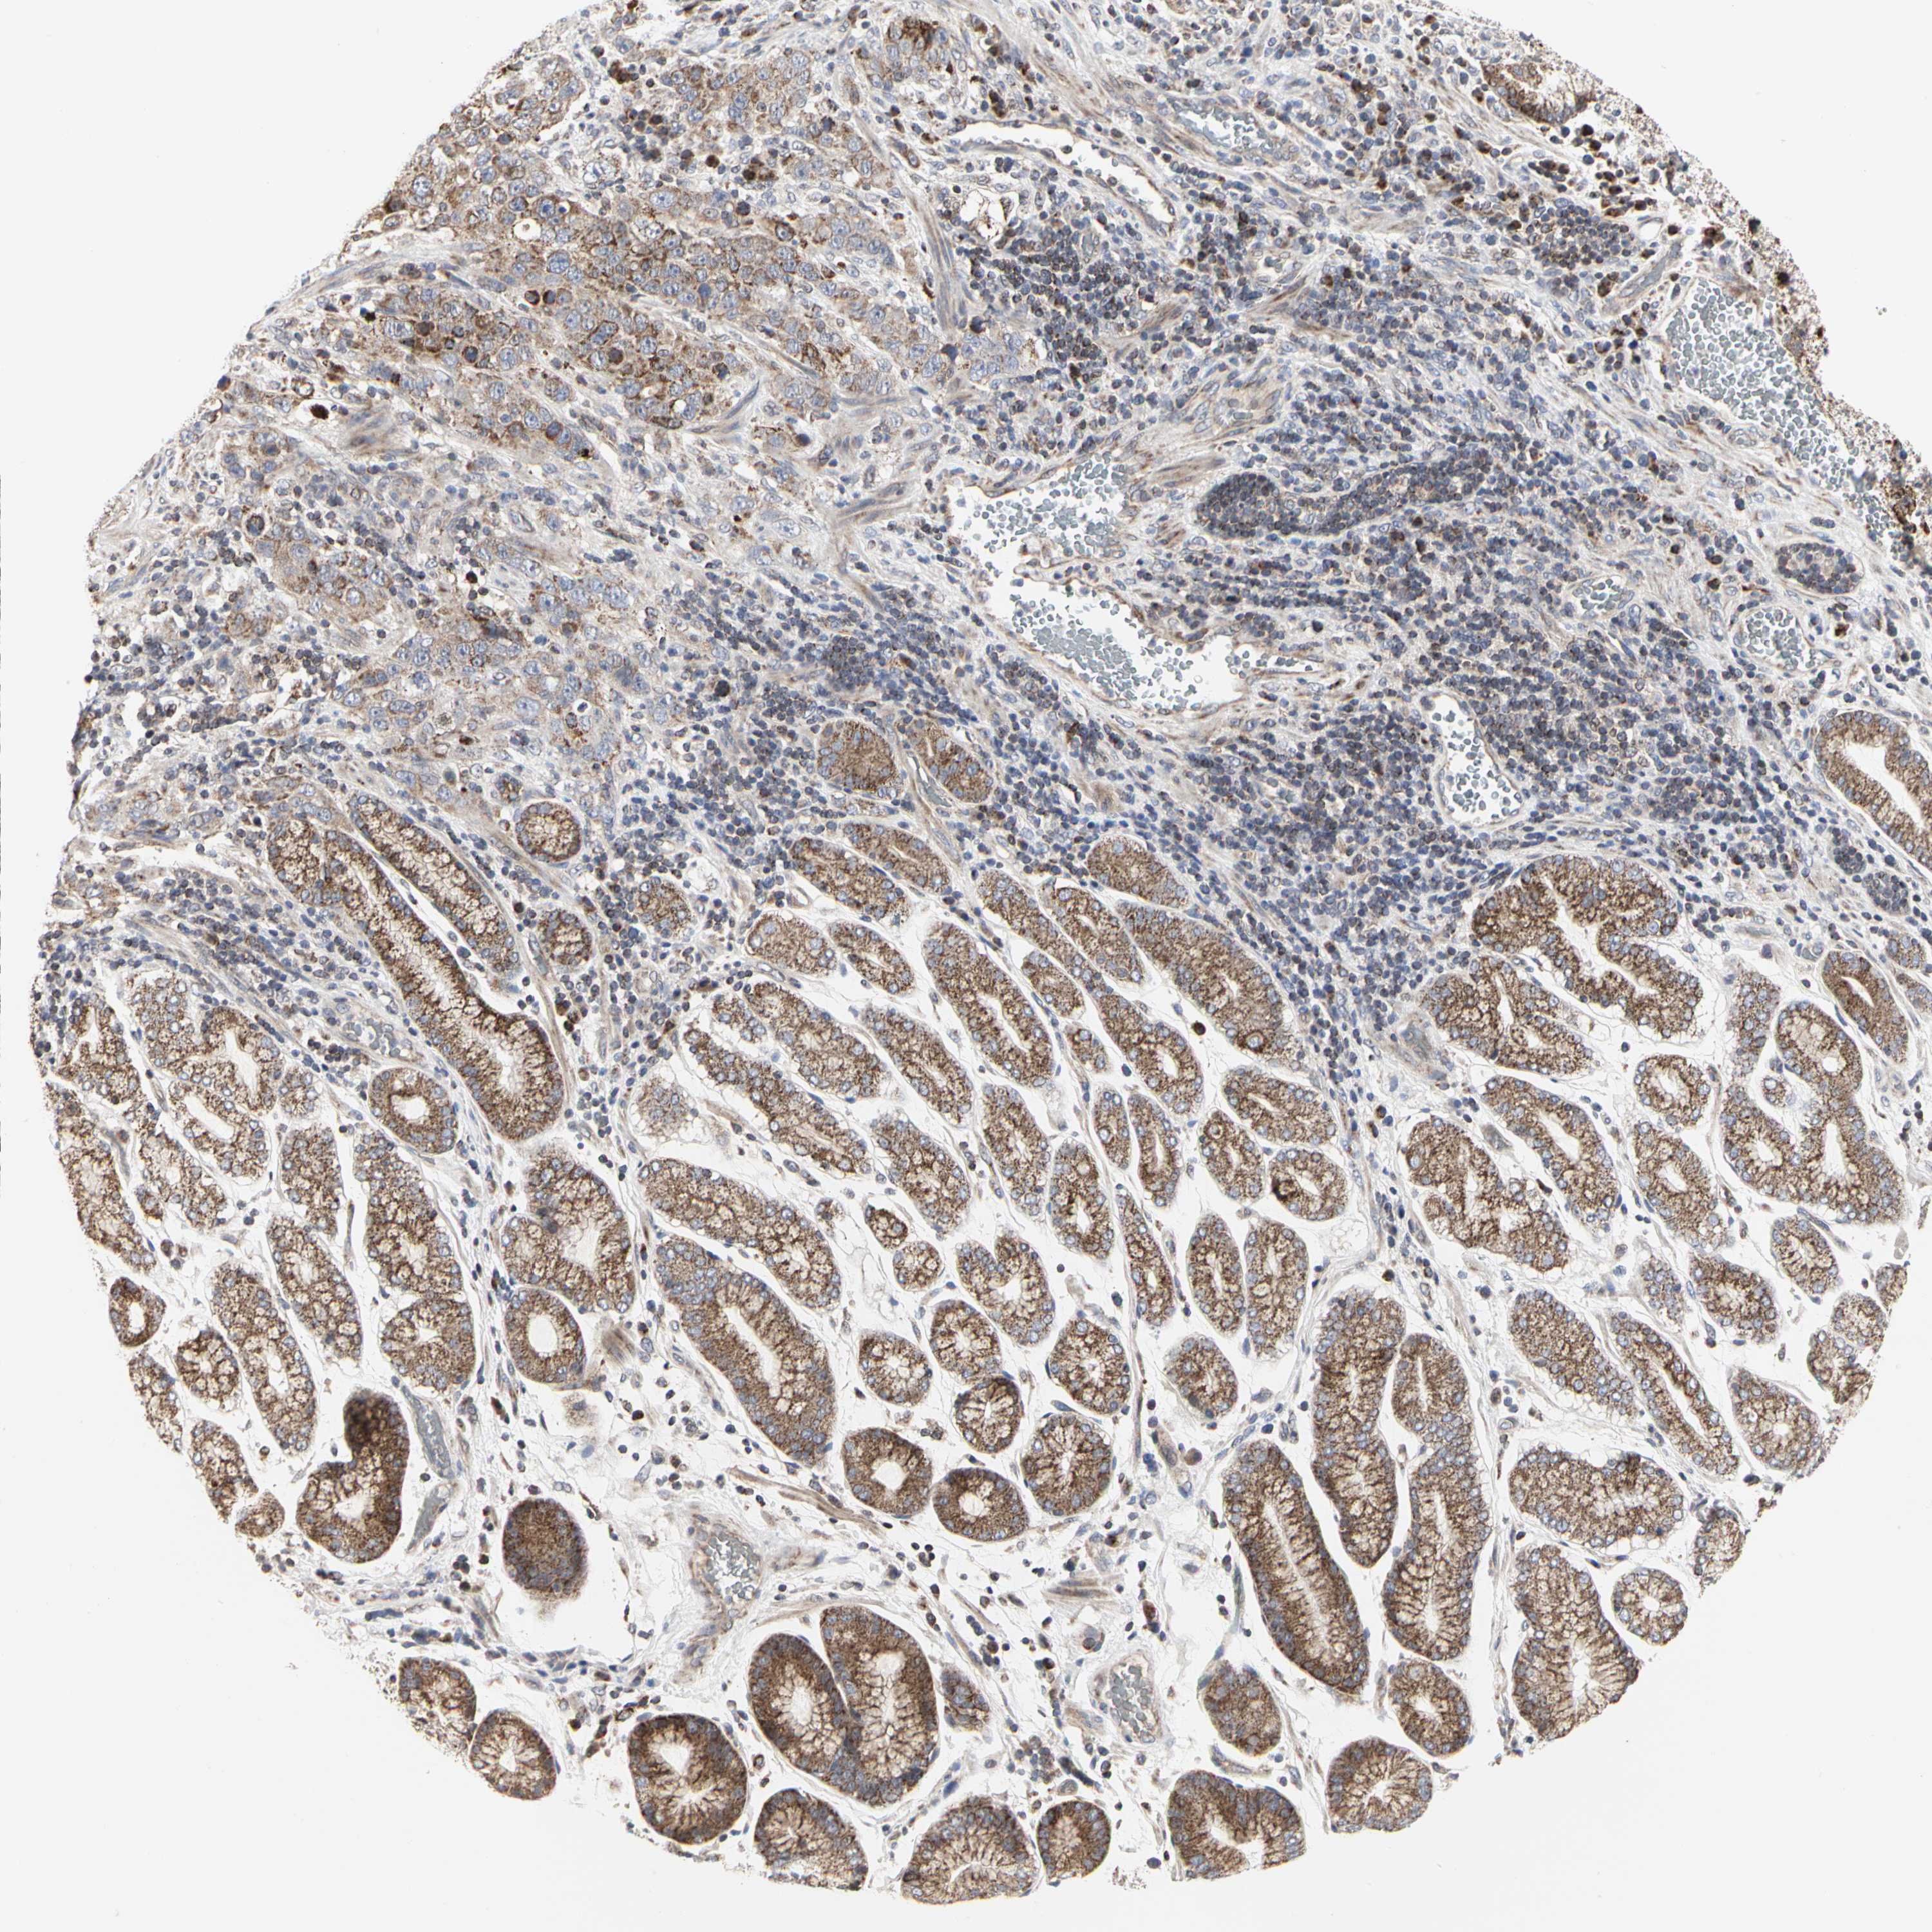

STOMACH CANCER - Protein expressioni

A mouse-over function shows sample information and annotation data. Click on an image to view it in a full screen mode. Samples can be filtered based on level of antibody staining by selecting one or several of the following categories: high, medium, low and not detected. The assay and annotation is described here.

Note that samples used for immunohistochemistry by the Human Protein Atlas do not correspond to samples in the TCGA dataset.

Antibody stainingi

Antibody staining in the annotated cell types in the current human tissue is reported as not detected, low, medium, or high, based on conventional immunohistochemistry profiling in selected tissues. This score is based on the combination of the staining intensity and fraction of stained cells.

Each image is clickable and will lead to virtual microscopy that enables deeper exploration of all samples and also displays staining intensity scores, fraction scores and subcellular localization as well as patient and tissue information for each sample.

Antibody HPA008164

Staining

High

Medium

Low

Not detected

Intensity

Strong

Moderate

Weak

Negative

Quantity

>75%

75%-25%

<25%

None

Location

Nuclear

Cytoplasmic/membranous

Cytoplasmic/membranous,nuclear

Adenocarcinoma, NOS